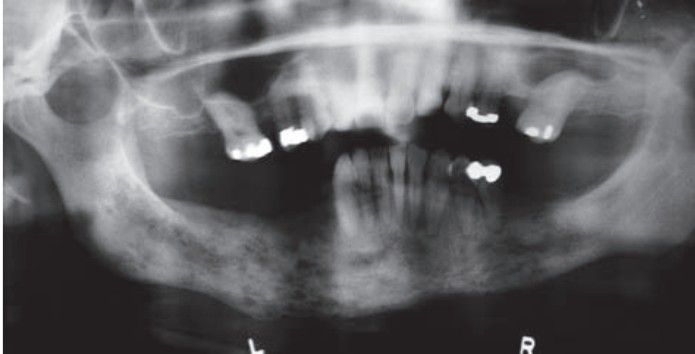

Chronic osteomyelitis of the mandible associated with periodontal disease. Note moth-eaten radiolucent appearance